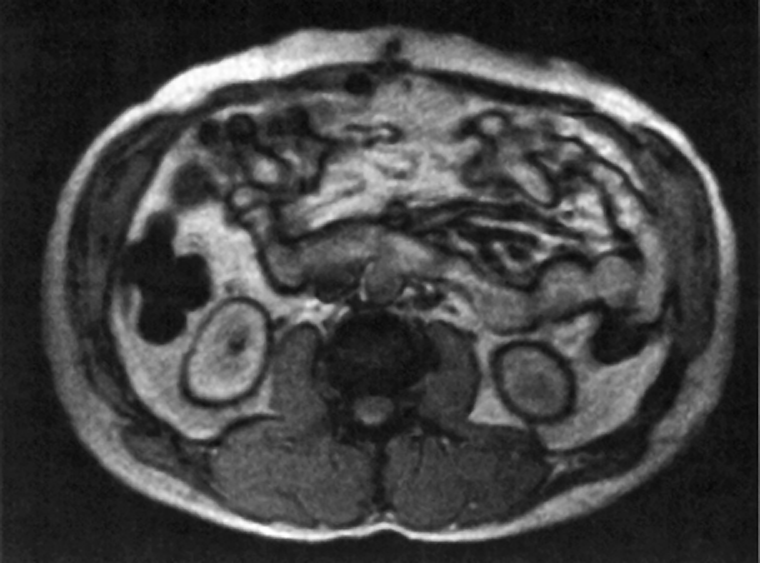

Figura 17-12:

Black boundary artifacts in the abdomen. Gradient-echo sequence with an echo time of 16 ms.